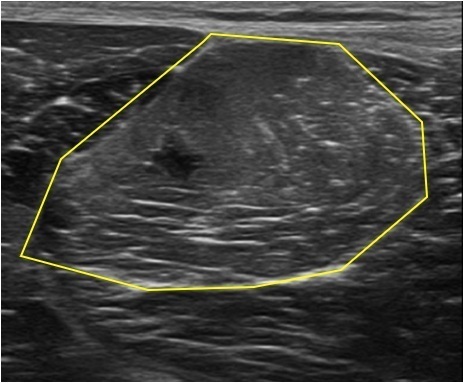

サッカーの切り替えし動作の際に右大腿後面に急に激痛を生じて痛めた、内側ハムストリングスの肉離れです。

症状、エコー画像から肉離れの奥脇分類2度損傷と考えられました。

エコー画像では黄色線の枠内の筋線維がその周囲の線維と比較して白く不鮮明に描出されている様子が分かります。

右内側ハムストリングスの肉離れ(○印)

エコー画像(短軸画像)